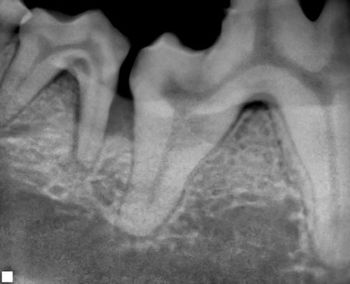

Veterinary dentist Dr. Christopher Snyder provides some tips for performing surgical extractions.